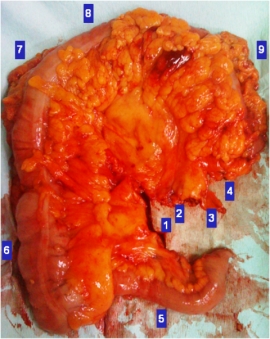

Ορισμός Τo τοξικό μεγάκολο περιγράφει την οξεία κολίτιδα, η οποία συνοδεύεται από συστηματικές τοξικές εκδηλώσεις και απεικονιστικά ευρήματα τμηματικής ή καθολικής μη αποφρακτικής διάτασης (> 6 εκατοστά σε διάμετρο) του παχέος εντέρου. Στη σύγχρονη κλινική ορολογία, αρμόζει καλύτερα ο όρος «τοξική κολίτιδα», αφού πολλοί ασθενείς αναπτύσσουν τοξικότητα, χωρίς την…